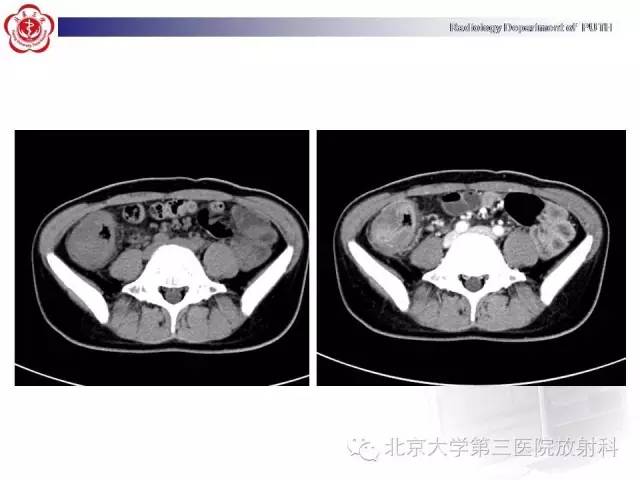

【病例】肠道白塞氏病1例X线CT